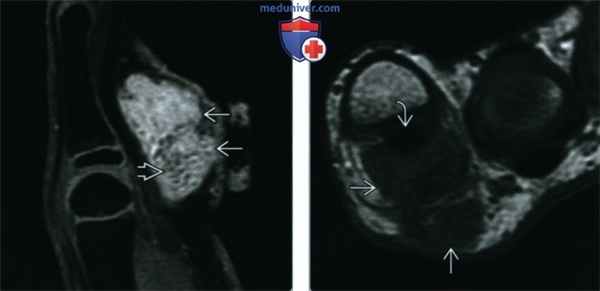

(Слева) При МРТ в сагиттальной плоскости на Т1ВИ вдоль ладонной поверхности пястно-фалангового сустава определяется образование с неровным нечетким контуром. Образование характеризуется изоинтенсивным сигналом по сравнению с мышцами и наличием гипоинтенсивных очагов. Следует отметить, что у этого ребенка открыта зона роста.

(Справа) При МРТ в сагиттальной плоскости на Т2ВИ в режиме FS выявленное инфильтративное образование характеризуется гетерогенно гиперинтенсивным сигналом и наличием рассеянных гипоинтенсивных очагов, соответствующих кальцификатам.

(Слева) При МРТ с контрастным усилением в сагиттальной плоскости на Т1ВИ в режиме FS определяется гетерогенное и достаточно интенсивное контрастирование выявленного образования. Небольшие очаги, соответствующие кальцитрикатам, неконтрастируются.

(Справа) При МРТ в аксиальной плоскости на Т1ВИ визуализируются инфильтративная структура и нечеткий контур кальцифицирующейся апоневротической фибромы. Образование прилежит к сухожилию сгибателя, что также характерно для гигантоклеточной опухоли и фибромы сухожильного влагалища. Однако перечисленные опухоли обычно имеют четкий контур.